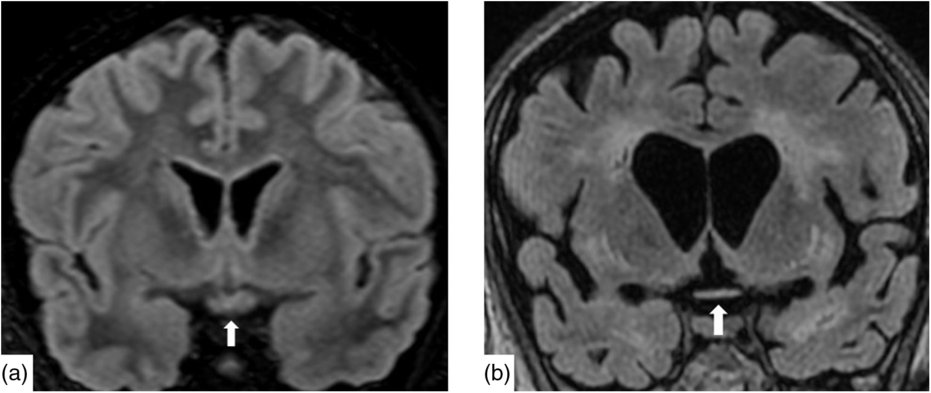

Nineteen days after admission pupils became sluggish, then 2 weeks later, became non-reactive to light with absent corneal and gag reflexes. Two months after presentation, he remained intubated and no objective determination of visual function could be obtained. Both pupils were fixed and unreactive to light. He also had bilateral lagophthalmos, severe dry eye and filamentary keratitis. Both optic discs were pale with circumpapillary high water marks suggestive of resolving optic disc oedema. In the left eye, there were flat white peripapillary retinal lesions extending into the macula, consistent with retinal nerve fibre layer infarcts. Repeat MRI demonstrated striking new T2W hyperintensity in the optic nerves (Figure 1b). Over 4 months, the retinal lesions gradually regressed followed by the high water marks, but the discs remained pale. The filamentary keratitis improved with aggressive lubrication and as he regained consciousness and the ability to blink. MRI 6 months after presentation revealed severe, global volume loss, including striking atrophy of the optic chiasm. There was also confluent, extensive signal abnormality throughout much of the brain (Figure 2). The patient was improving clinically but unexpectedly died 10 months after admission to hospital from respiratory complications.

Figure 2: Coronal reconstruction of a volumetric Fluid-Attenuated Inversion Recovery (a) demonstrating normal signal and morphology of the optic chiasm. Contrast with 6 months after presentation (b) demonstrating severe atrophy of the chiasm and global volume loss. There is new severe white matter signal change in much of the imaged brain.